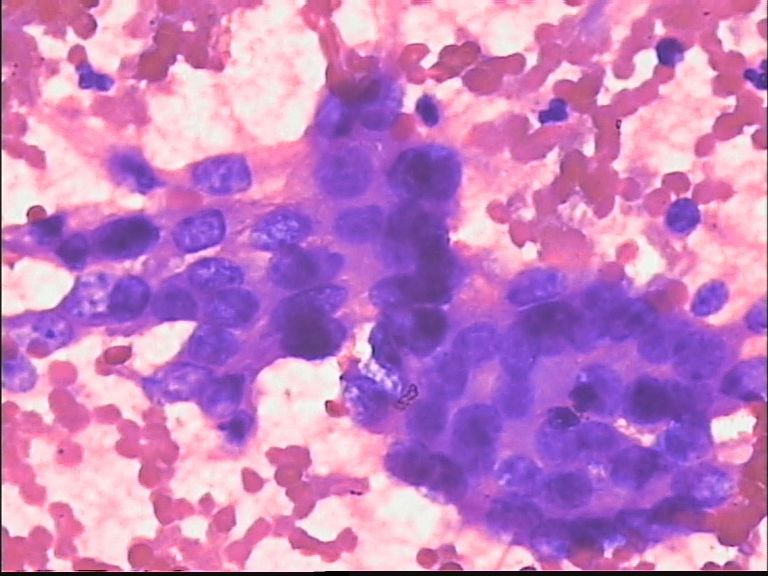

男 70岁,ct肺部见一肿块:结核?肺癌?

未发现明显恶性细胞  好像有多核巨细胞 ?认为 本例要进一步检查除外结核

恶性不能除外

考虑癌。

这个病例有些深染染色质粗异型的核,后边几幅图似乎是退变的多核巨细胞;结核或恶性都不能除外;一般遇到这样的病例我会选择报:见少许深染异型细胞及多核巨细胞;建议穿刺组织活检以进一步排除结核或恶性之可能。

支气管镜活检看到的是粘膜慢性炎伴多核巨细胞反应。

我个人看法是:涂片内未见癌细胞。请注意,一些核略大深染的核都有终板,应该是反应性的支气管粘膜上皮细胞。

未见恶性细胞。